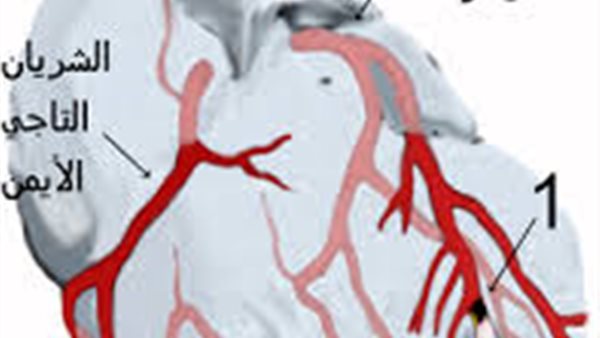

في إنجاز طبي جديد ، تمكن فريق طبي متخصص من إنقاذ حياة شاب يبلغ من العمر 18 عامًا بعدما أصيب بـ جلطة حادة في الشريان التاجي الأمامي، وهي من الحالات الخطيرة التي تهدد الحياة إذا لم يتم التعامل معها بسرعة ودقة.

وصل المريض إلى مستشفى طهطا العام في محافظة سوهاج في حالة حرجة ومتأخرة نسبيًا، وعلى الفور جرى تشكيل فريق طبي متكامل، حيث تم إجراء الفحوصات القلبية المتخصصة التي أظهرت وجود انسداد كامل في الشريان الأمامي الرئيسي للقلب.

قرر الأطباء التدخل الفوري بإجراء قسطرة قلبية عاجلة لاستكشاف الشرايين التاجية، وتمكن الفريق الطبي من فتح الشريان المسدود وتركيب دعامة معدنية بنجاح، مما أعاد تدفق الدم إلى عضلة القلب وأنقذ حياة المريض في اللحظات الأخيرة.